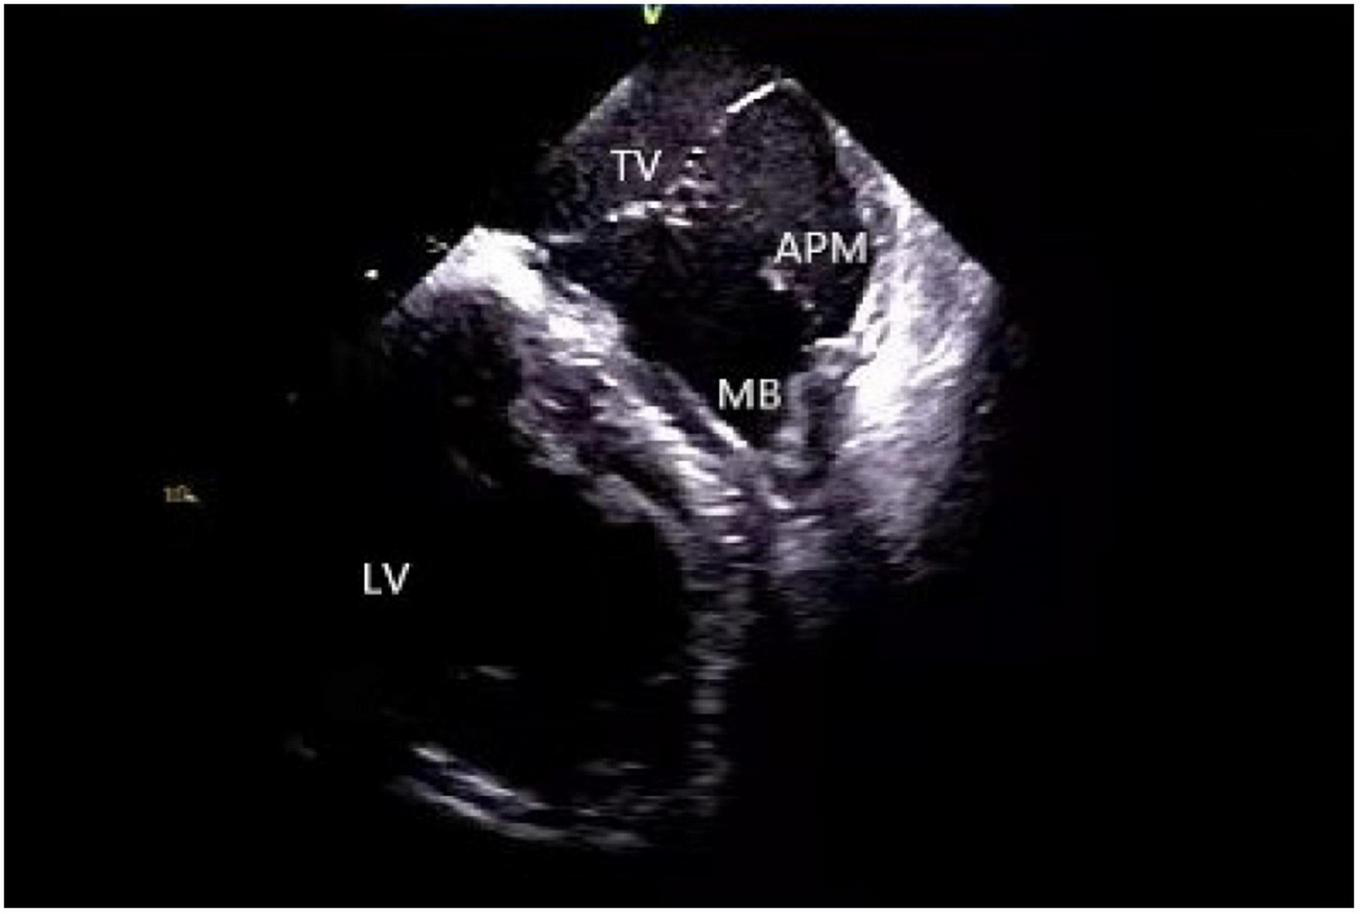

Application of intracardiac echocardiography in ablation of arrhythmias originating from moderator band

A moderator band is a muscular band located in the mid to apical RV that connects the interventricular septum to the RV-free wall, supporting the anterior papillary muscle. It typically contains an RBB subdivision and is one of the possible origin sites for arrhythmias (31, 40). Using a 3D mapping system alone for the ablation of moderator band arrhythmias is not highly effective due to uncontrollable stability as well as mapping and ablation catheter arrival rate. ICE is particularly useful in such cases as it clearly shows the anatomical structures adjacent to the moderator band, which is helpful for mapping and ablation. Furthermore, the construction of the long and short-axis views of the moderator band can clearly define the position of the band body, the septal and the anterior papillary muscle insertion points, and monitor the attachment and stability of the catheter and the target tissue in real-time (11, 41) (Figure 8).

FIGURE 8

Moderator band. TV, tricuspid valve; LV, left ventricle; APM, anterior papillary muscle; MB, moderator band.